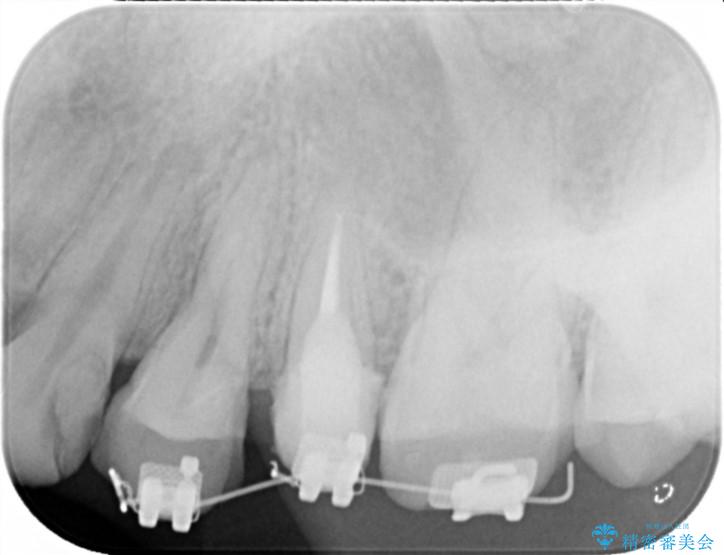

- 歯ぐきの腫れや、歯の内部が黒く見えることからの虫歯の治療を求めて来院されました。

虫歯が大きかったことから、神経の温存はできたものの歯ぐきよりも深い虫歯の問題を解決するため部分矯正治療を併用したセラミック治療を行うこととしました。

当初、歯ぐきよりも深い虫歯のぞんざいや、歯のポジションに問題がありましたがマルチブラケットを用いた部分矯正を行うことで適切な位置へと歯を移動させ、歯周環境を整えたセラミック治療を行うことができました。